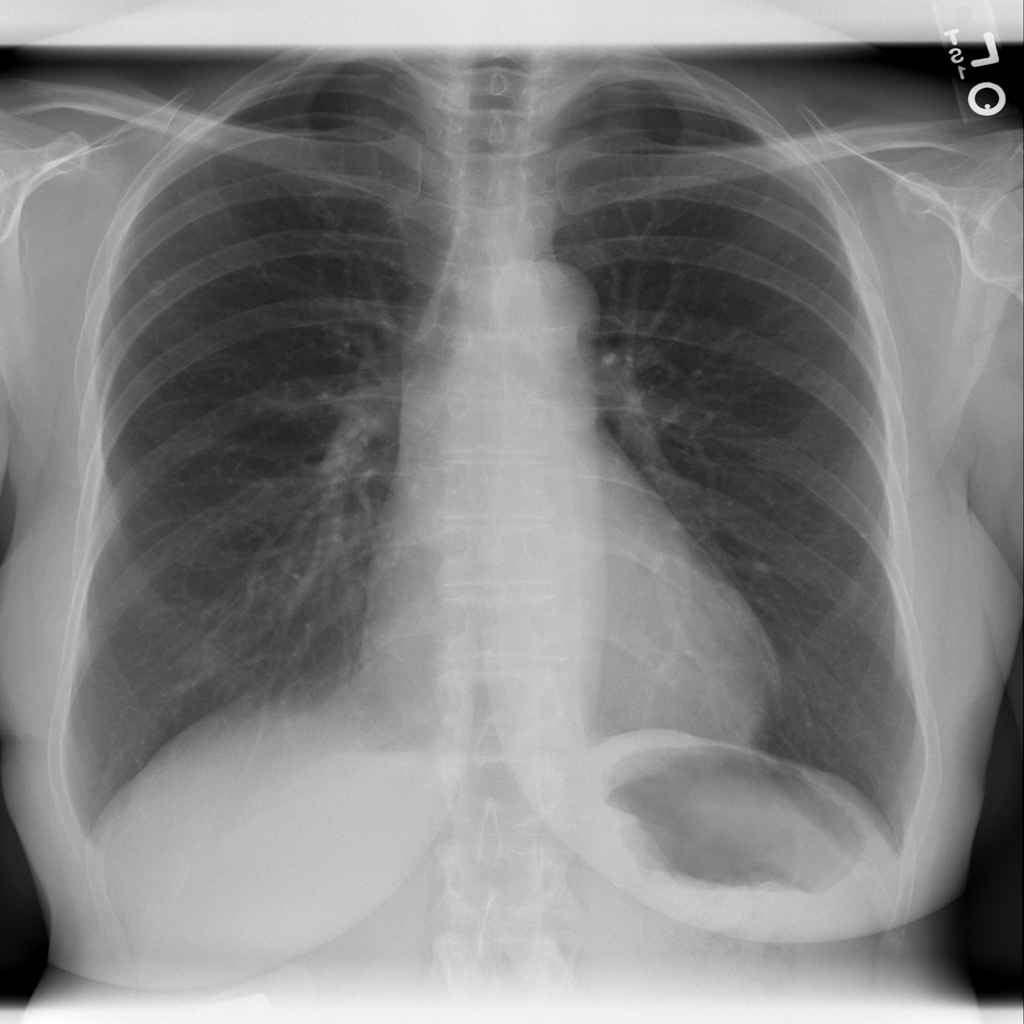

Showing up to 90 reference images for Nodule.

PAT-F3E7 · IMG-002Nodule

PAT-F3E7 · IMG-002

PA